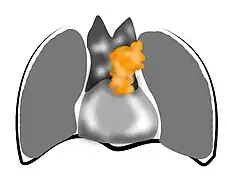

Présentation tomodensitométrique classique d'un thymome à un stade précoce (cercle rouge). À l'arrière, l'aorte, la veine cave supérieure et l'artère pulmonaire sont visibles en coupe. Scanner injecté, en fenêtre médiastinale, montrant un carcinome thymique envahissant les structures médiastinales :

Scanner injecté, en fenêtre médiastinale, montrant un carcinome thymique envahissant les structures médiastinales :

1 : tumeur hétérogène, aux contours irréguliers, présentant des plages hémorragiques ;

2 : veine cave supérieure ;

3 : tronc artériel brachiocéphalique ;

4 : artères sous-clavière gauche et carotide commune gauche ;

5 : crosse de l'aorte ;

6 : sternum. Scanner en fenêtre parenchymateuse, montrant un carcinome thymique envahissant les poumons (avec des lésions d'emphysème) au contact des deux poumons (1 : poumon droit ; 2 : poumon gauche) ;